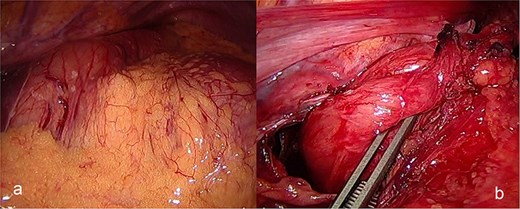

The patient was admitted under the care of the general surgery department, and he was taken to the operating room for a laparoscopic exploration, which showed mesenteroaxial gastric volvulus, wandering spleen, and a large hiatal hernia which was ~5 cm in size. No devitalized tissues were found. An attempt at intraoperative endoscopy failed to pass through the hiatus. A cruroplasty with a Toupet fundoplication and gastropexy were done as shown in (Figs 3 and 4). On the third postoperative day, the patient was doing well. He was tolerating oral intake and passing regular motions and was discharged home in good condition as he was traveling to his country.

(a) Intraoperative image revealing the position of the stomach without any devitalized tissue. (b) A large hiatal hernia after completion of dissection in preparation for cruroplasty with a Toupet fundoplication.